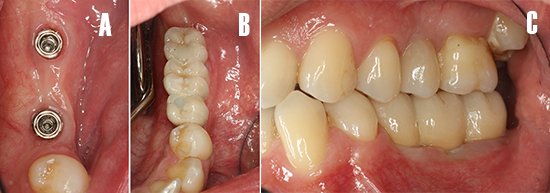

Tras un periodo de osteointegración de tres meses se realizó una cirugía de acceso para colocar el pilar de cicatrización de implante 3.7 y posterior registro con escáner intraoral (3shape Trios®, Copenaghen, Denmark) (Fig. 13), para la confección de la prótesis atornillada definitiva (Fig. 14)

Figura 13. Fase protésica. A) A las 12 semanas de la cirugía de implantes, se realizó una segunda cirugía para colocar el pilar de cicatrización a nivel de 3.7. B) Pilar de cicatrización atornillado. C) A los 15 días se procede tomar registros de impresión con un escáner intraoral. Nótese los scan-bodies en posición.

Figura 14. Fase protésica. Imágenes intraorales. A) Vista oclusal de la salud de los tejidos periimplantarios el día de colocación de la prótesis. B) Vista oclusal de la prótesis ceramo-metálica atornillada. C) Vista lateral de la prótesis definitiva, nótese el esquema oclusal de la restauración.